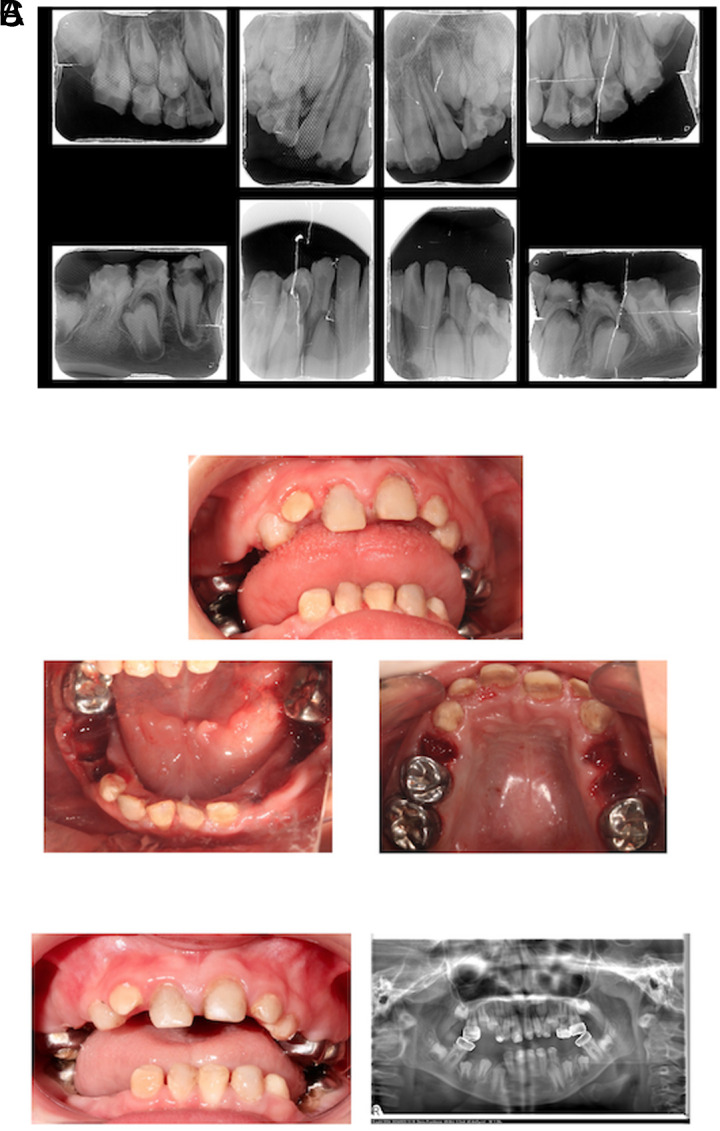

Kohlschütter-Tönz综合征(KTS) (OMIM#226750)是一种罕见的常染色体隐性遗传病,其特征为癫痫性脑病、发育迟缓和淀粉样变性不全。早期诊断和治疗至关重要,但症状的复杂性,特别是牙齿和神经损伤,构成了重大挑战。本报告的目的是描述2个兄弟姐妹的临床表现和他们的牙科管理,他们的牙科检查导致遗传转诊和随后诊断为KTS。牙科检查显示,两名兄弟姐妹的牙釉质缺陷与淀粉原性不完全性一致,包括黄棕色变色,软牙釉质和裂口。弟妹,一名9岁男孩,表现为早发性癫痫、智力残疾、痉挛和肾结石病史。哥哥是一名13岁的男孩,表现出更严重的神经发育迟缓、早发性癫痫和耐药性癫痫。基因检测证实了ROGDI基因的纯合缺失,从而在两个兄弟姐妹中诊断为KTS。弟弟妹妹在全身麻醉下接受了成功的恢复性治疗,而哥哥姐姐的口腔护理由于全身麻醉的禁忌症而被保守管理。这些病例强调了儿科牙医在早期识别罕见遗传疾病(如KTS)中的重要性,特别是当存在牙齿畸形(如无晶面发育不全)时。及时转诊进行遗传评估可以促进准确的诊断和适当的护理计划。此外,分享临床经验和治疗结果有助于更好地了解这种罕见综合征,并有助于指导未来的诊断和治疗策略。

Kohlschütter-Tönz syndrome (KTS) (OMIM#226750) is a rare autosomal recessive disorder characterized by epileptic encephalopathy, developmental delay, and amelogenesis imperfecta. Early diagnosis and management are crucial, but the complexity of symptoms, particularly dental and neurological impairments, poses significant challenges. The aim of this report is to describe the clinical findings of 2 siblings and their dental management, whose dental examination led to genetic referral and subsequent diagnosis of KTS. Dental examinations revealed enamel defects consistent with amelogenesis imperfecta, including yellow-brown discoloration, soft enamel, and diastemas in both siblings. The younger sibling, a 9-year-old boy, exhibited early-onset seizures, intellectual disability, spasticity, and a history of kidney stones. The older sibling, a 13-year-old boy, presented with more severe neurodevelopmental delay, early-onset seizures, and drug-resistant epilepsy. Genetic testing confirmed homozygous deletions in the ROGDI gene, leading to the diagnosis of KTS in both siblings. The younger sibling received successful restorative treatment under general anesthesia, while the older sibling's oral care was managed conservatively due to contraindications for general anesthesia. These cases underscore the importance of pediatric dentists in the early identification of rare genetic disorders such as KTS, especially when dental anomalies like amelogenesis imperfecta are present. Timely referral for genetic evaluation can facilitate accurate diagnosis and appropriate care planning. Moreover, sharing clinical experiences and treatment outcomes contributes to a better understanding of this rare syndrome and helps guide future diagnostic and therapeutic strategies.